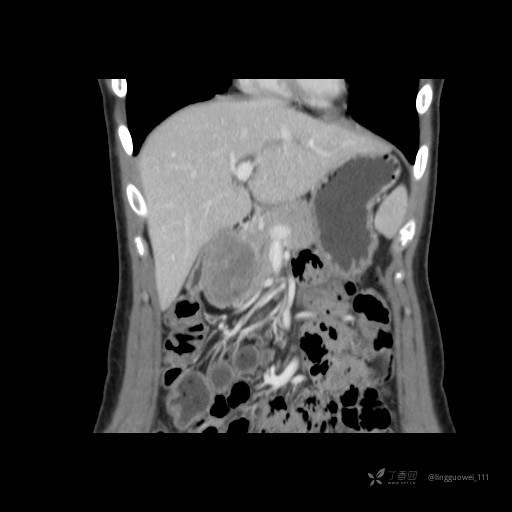

患者性别:女

患者年龄:28岁

主诉:体检发现胰腺病变,行 CT检查。

门脉期:

img